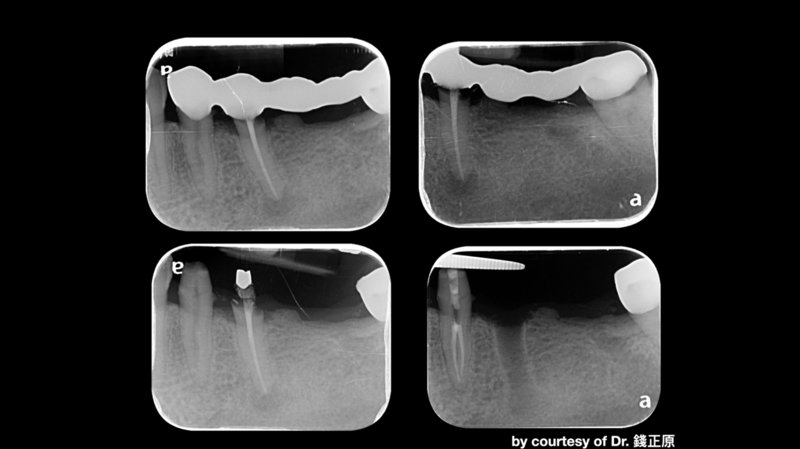

治療的開始是我們幫病患解決了疼痛,從病患腫痛,拆假牙、拔牙,恰好左下第一小臼齒為根管難症,仰賴錢正原醫師的成功顯微根管治療,取的病患的信任。接著我們一步步的重建,也因為這區是長達十幾年的五單位牙橋,拆掉後除了病患明顯左邊不好咀嚼,因此對於重建有強烈的企圖心,另外我們也看到因為長久缺牙而有牙脊萎縮,並伴隨角質化上皮缺損。缺損的骨頭部分我們是補得回來的,但一次三顆植體加上水平補骨,若在缺角質化上皮的這區手術,總覺得風險高了些。因為若有足夠的角質化上皮,可以讓我們植牙手術補骨縫合時,將縫線進針在角質化上皮內,縫線與角質化上皮內就像釘書針扎實的釘錨著,能對抗術後腫脹期防止傷口裂開,讓手術更能保證成功; 另外,若於其後補上骨粉和再生膜後,牙脊上的角質化上皮也相對穩定,不會在咀嚼時移動,讓其下方的骨粉可以好好轉換成自體骨; 角質化上皮的功能不只如上,在將來植體接假牙出來後,在咀嚼時,也因有足夠角質化上皮的包覆,能防止食物掉入和植體相接的牙肉內,防止植體周圍炎的產生。談到植體周圍炎的預防,植體植入的位置,最好平行假牙咬合軸向的受力,並且出孔位置在假牙的正中心。

以這個案例,我們量測了牙脊缺牙區的總寬度,再精算植體間距和植體寬度,後牙區小臼齒種植寬度長度4 mm X 11.5mm的植體,大臼齒則置入兩支寬度長度5 mmX11.5mm的植體,而在設計時在軟體內要讓三顆植體盡可能平行,以利將來植牙贋復製作,減少應力集中造成植體周圍炎的可能。我們利用模子的STL檔和斷層掃描的DICOM檔做疊合,在Bluesky軟體內,由醫師自己設計出最佳的植體位置、寬度長度,再請專業的3D列印公司做數位模板輸出。因為在軟體內我們已經看出將來植體的位置和需補骨的量,進而反推切線的位置,最後我們知道角質化上皮終究都需要補一場,於是治療計畫一開始就是先補上角質化上皮,等四個月後軟組織穩定,我們接著利用手術導板植入三個植體,並於當次補入骨粉和再生膜,術後如我們預期,傷口恢復良好。